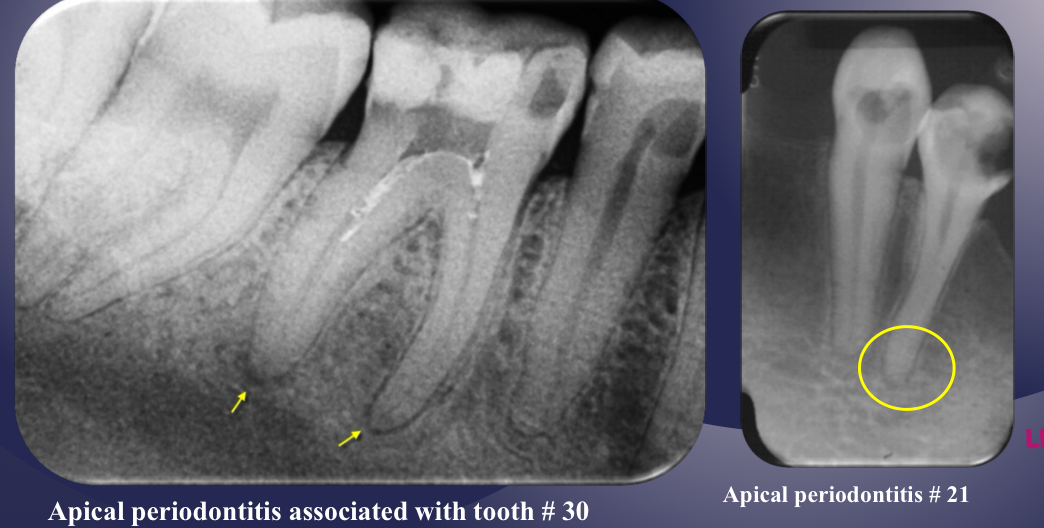

radiographic signs:

widened PDL space

loss of lamina dura

apical periodontitis

lack of continuous lamina dura, initial signÂ

apical periodontitisÂ

early periapical lesion

widening of PDL space, thickening of LD